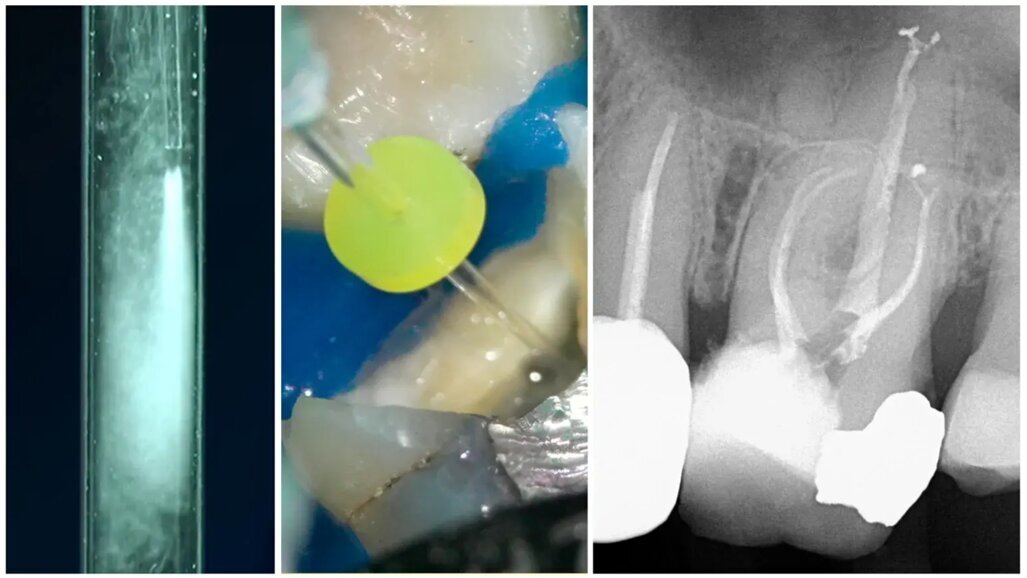

Д-р Benedict Bachstein от Exclusively Endodontics в Ню Джърси сподели клиничния си опит с OdneClean. Той и екипът му вече са извършили стотици процедури, използвайки устройството. Примерите, които той представи, подчертават способността на OdneClean да открива и почиства латерални и допълнителни канали, дори при витални зъби. OdneClean е показал висока ефективност и при почистването на съединени коренови канали.

Д-р Jenny He от Associates in PIE и доцент в Тексас A&M University College of Dentistry, представи ежедневната клинична ефективност на OdneClean. Тя е документирала над 50 клинични случая в платформата на Odne и демонстрира възможностите на устройството за бързо и цялостно почистване при ретрийтмънт. Тя подчерта, че премахването на остатъци от силър и гутаперка е значително улеснено и похвали способността на OdneClean да почиства дълги, тесни и извити канали.

Д-р Brett E. Gilbert от King Endodontics в Найлс, Илинойс, представи спешен случай на необратим пулпит и симптоматичен периапикален периодонтит. Почистващият процес бил извършен само с вода чрез OdneClean, без натриев хипохлорит. При последващо наблюдение пациентът почти не е съобщил за дискомфорт. Д-р Gilbert е използвал OdneClean в над 100 случая заради мощното му измиване, което му позволява да използва по-малко хипохлорит и намалява риска от токсичност и увреждане на тъканите. Той също така комбинира OdneClean с лазери в зависимост от случая.

Д-р Jerome Stroumza от Spruce Dental в Сан Франциско и собственик на EndoImplantology Institute сподели, че използва OdneClean и OdneFill в практиката си. Според него OdneClean е много полезен за откриване и почистване на мезиални канали, а OdneFill предлага надеждно и висококачествено запълване. Тази комбинация представлява нова парадигма в ендодонтията, позволявайки почистване и запълване на сложни морфологии без необходимост от оформяне на канала по форма на конус.